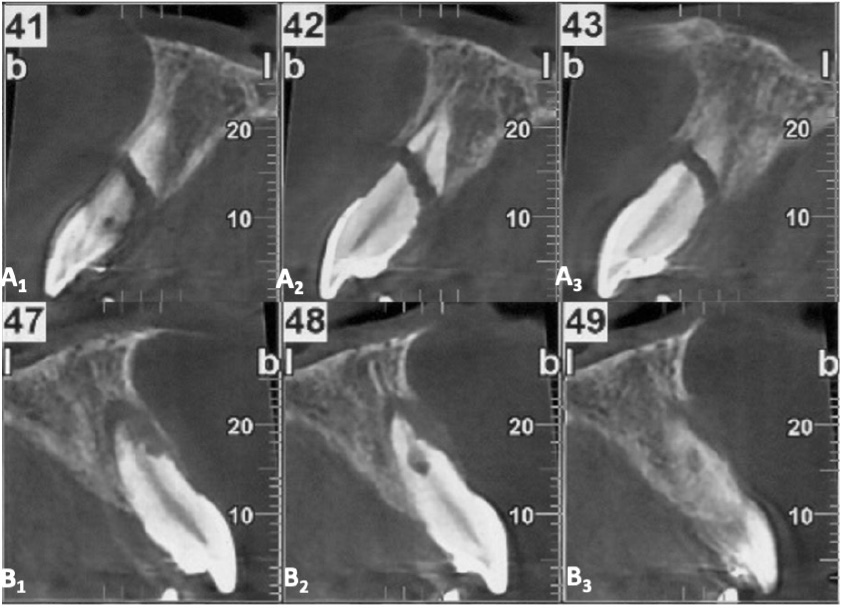

Cone beam computed tomography (CBCT) may often be required as a follow-up to assess the involvement of surrounding tissues, the amount of external and internal root resorption on the involved teeth, the anatomy of the root fracture of the apical third, and displacement of the coronal segment. Figure 2 and Figure 3 illustrate CBCT parasagittal images that confirm the results of the intraoral radiographs. The diastasis between the coronal and apical fragments of #11 appear to be more evident on the fracture line and the presence of a “new apical foramen” is highlighted. In addition, areas of external inflammatory resorption on the apical fragment are evident and the fracture line appears jagged. The images relating to #21 appear suggestive for external inflammatory resorption, particularly on the vestibular side, which is the site of concomitant bone inflammation in the parasagittal image #48. Internal pulp resorption can also be observed at the apical third of the root.